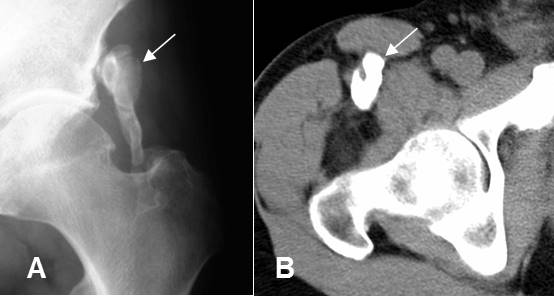

Fig 153. Miositis osificante.

A: Rx de cadera y B: TAC axial. 2 casos diferentes donde existe calcificación de tejidos blandos en relación con grupos musculares, por miositis osificante.